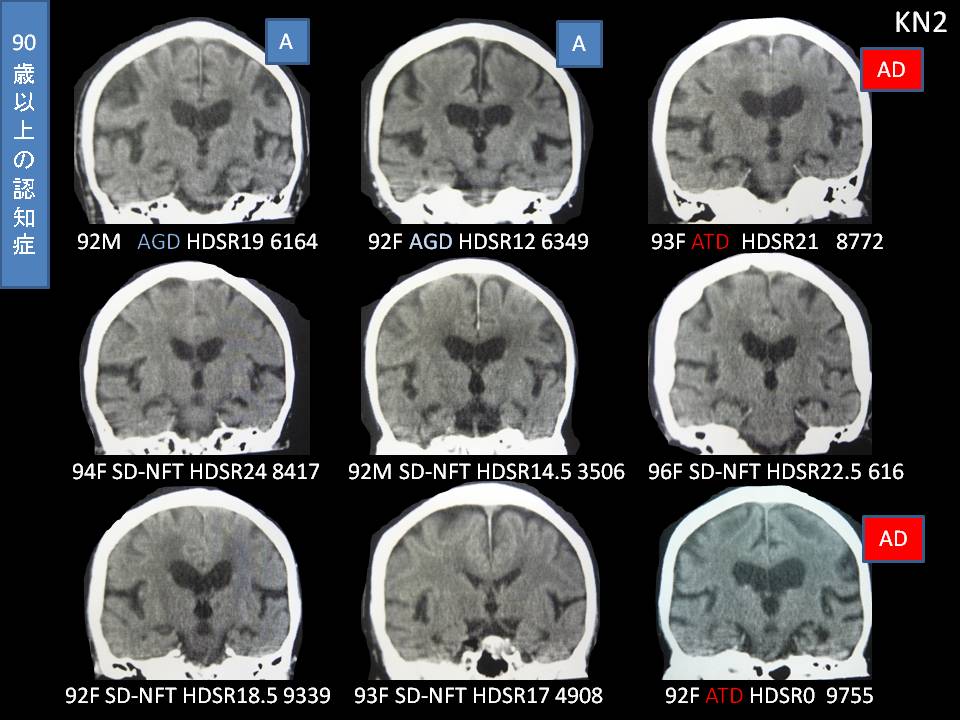

CMI(側脳室体部幅)で見てゆく認知症病型(たらこ・ちまき)

今週号は、たらことチマキの話を特集します。CT水平断で側脳室体部がたらこに見えるのは、だいたいCMIが30%を超したあたりからです。たらこにみえるのは、脳室拡大型のアルツハイマー型認知症と正常圧水頭症です。30%を超す患者は少ないですが、たらこならアルツハイマーだという意味です。前角が優位に拡大するのはチマキと呼び、ピック病です。逆に後角が拡大するのはアルツハイマーを決定づける所見で、逆チマキと言ってもよいでしょう。なぜ決定づけるかと言いますと、人間は生理的に前頭葉が萎縮しやすく、後角優位に拡大するのは非常に病的で、後方型認知症しかおきえないからです。